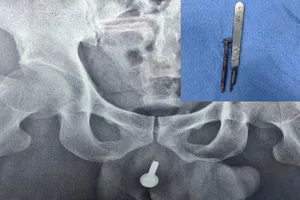

Đi cấp cứu vì bị bạn nhậu nhét đinh vít 6cm vào đường tiểu